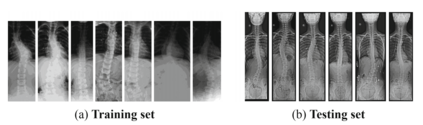

Scoliosis is a sideways curvature of the spine that most often is diagnosed among young teenagers. It dramatically affects the quality of life, which can cause complications from heart and lung injuries in severe cases. The current gold standard to detect and estimate scoliosis is to manually examine the spinal anterior-posterior X-ray images. This process is time-consuming, observer-dependent, and has high inter-rater variability. Consequently, there has been increasing interest in automatic scoliosis estimation from spinal X-ray images, and the development of deep learning has shown amazing achievements in automatic spinal curvature estimation. The main target of this thesis is to review the fundamental concepts of deep learning, analyze how deep learning is applied to detect spinal curvature, explore the practical deep learning-based models that have been employed. It aims to improve the accuracy of scoliosis detection and implement the most successful one for automated Cobb angle prediction. Keywords: Scoliosis Detection, Spinal Curvature Estimation, Deep Learning. i